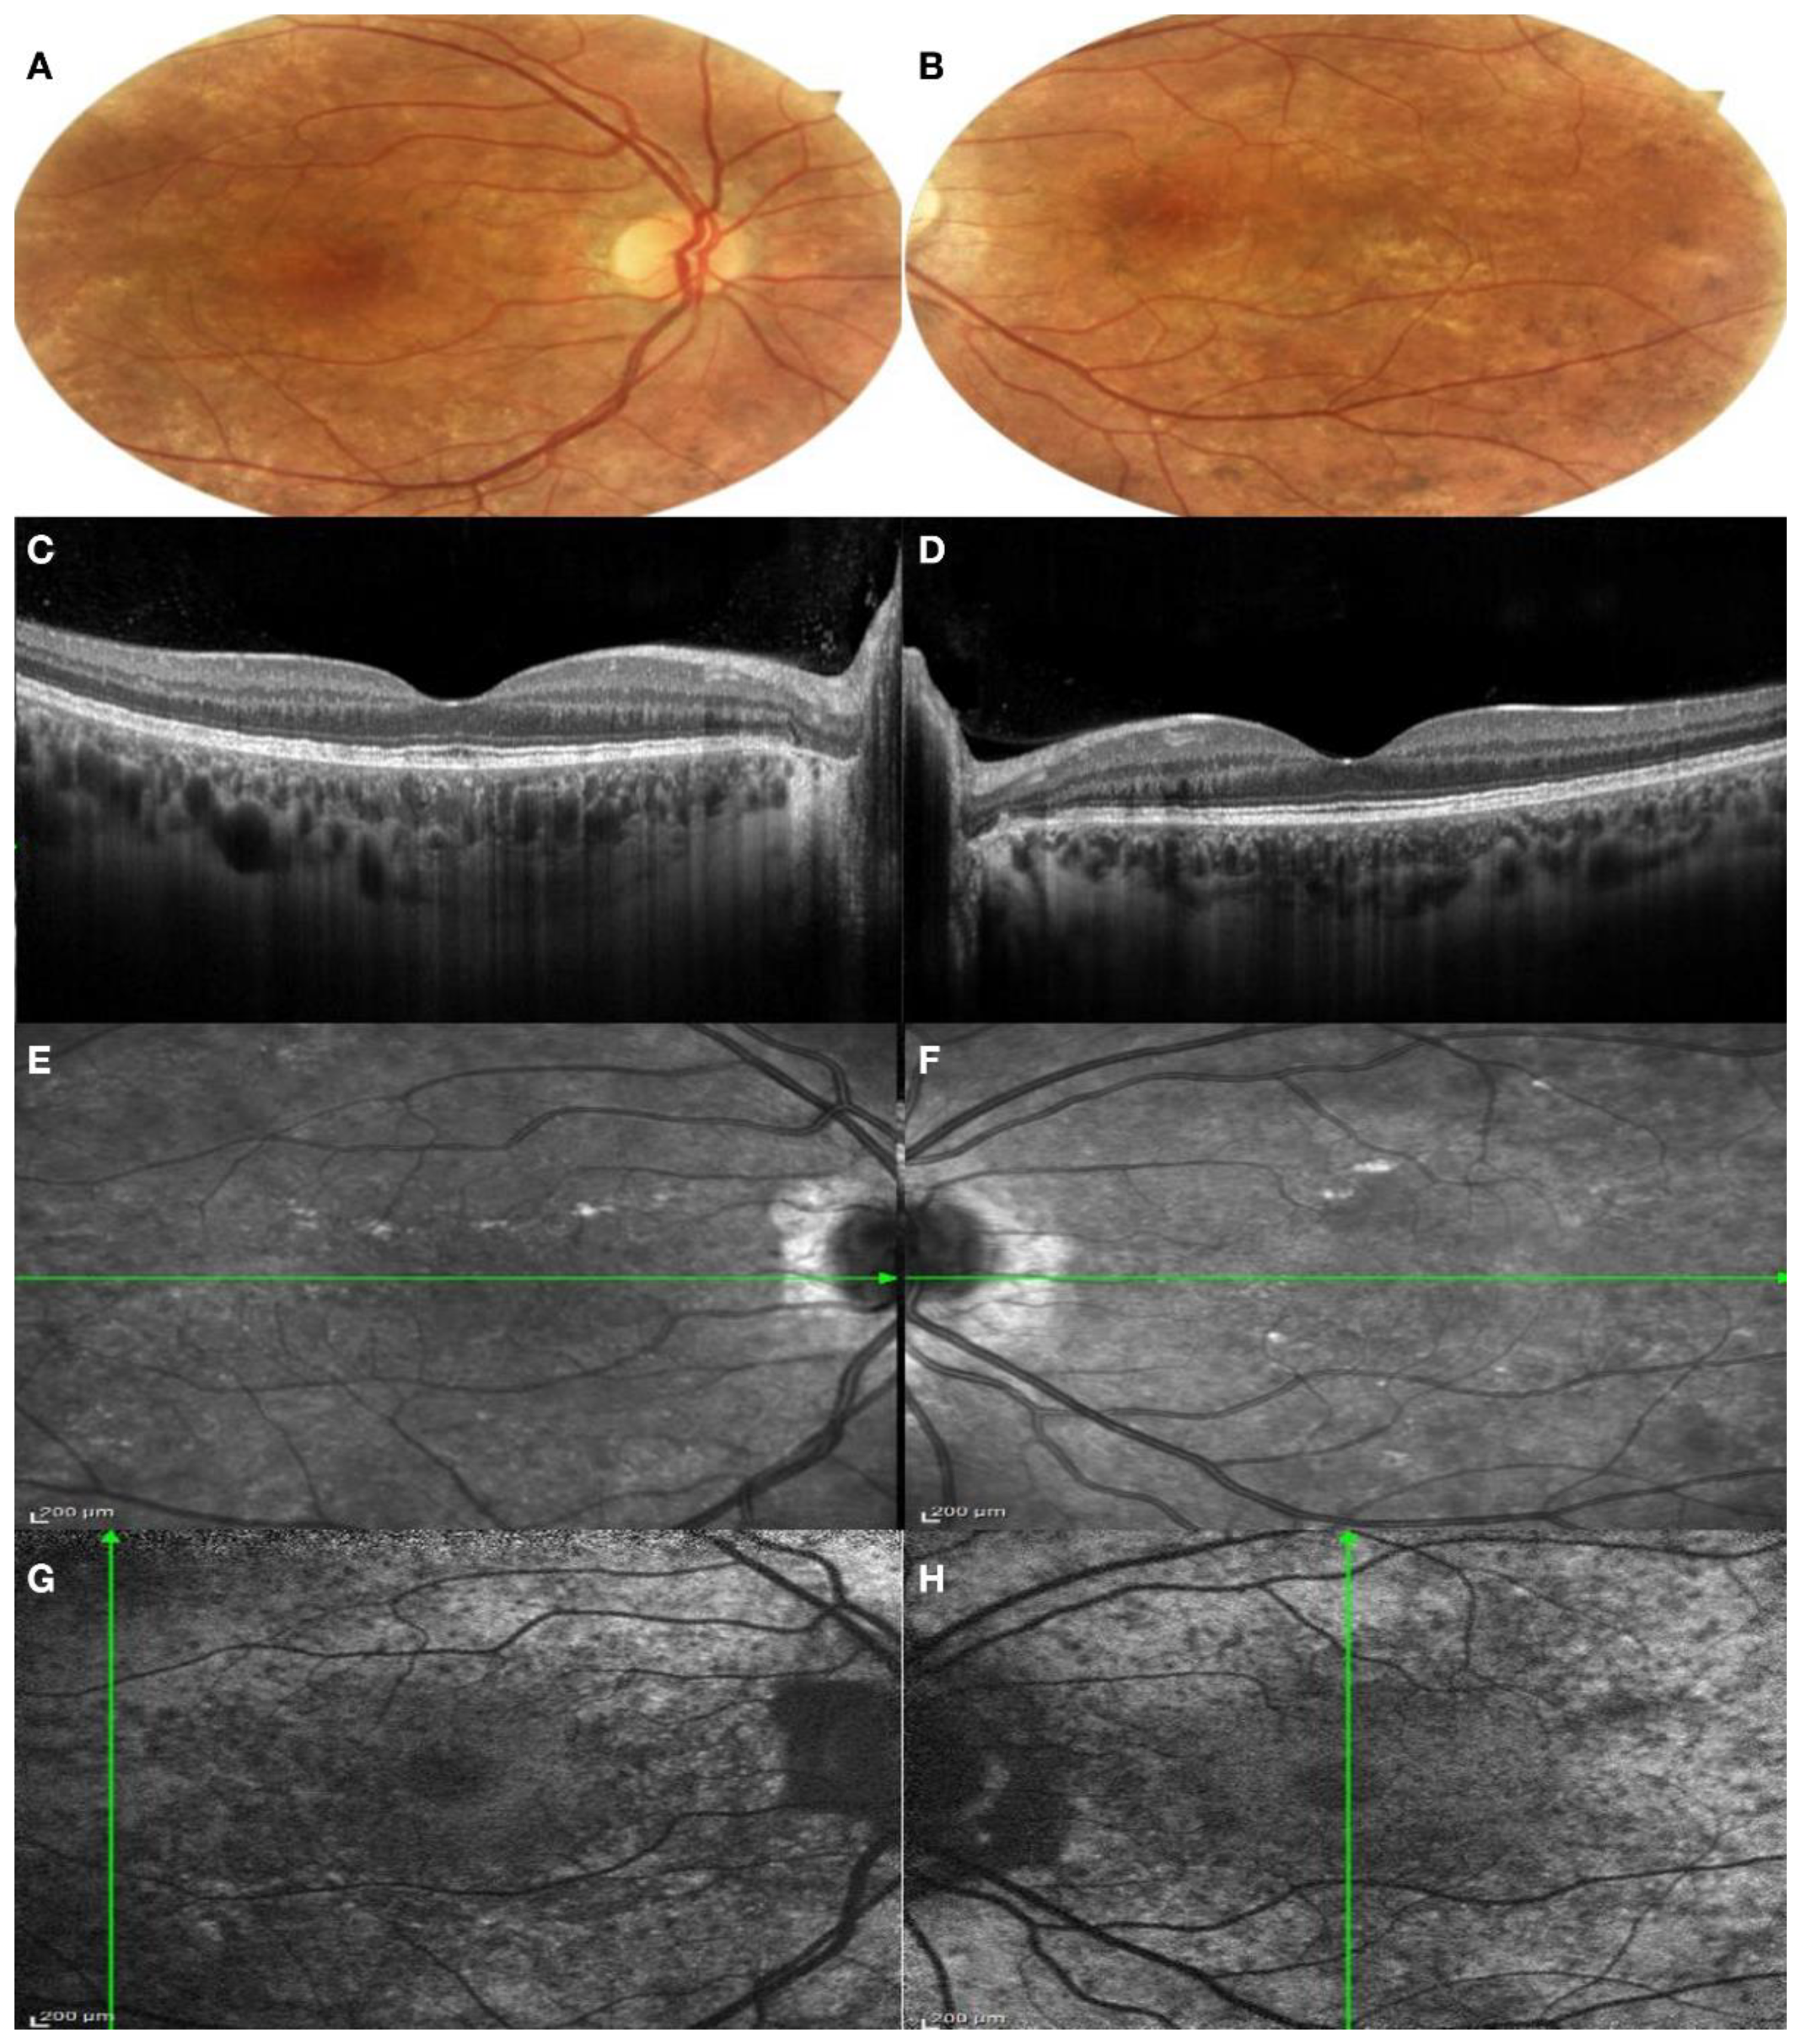

3.1. Clinical Findings